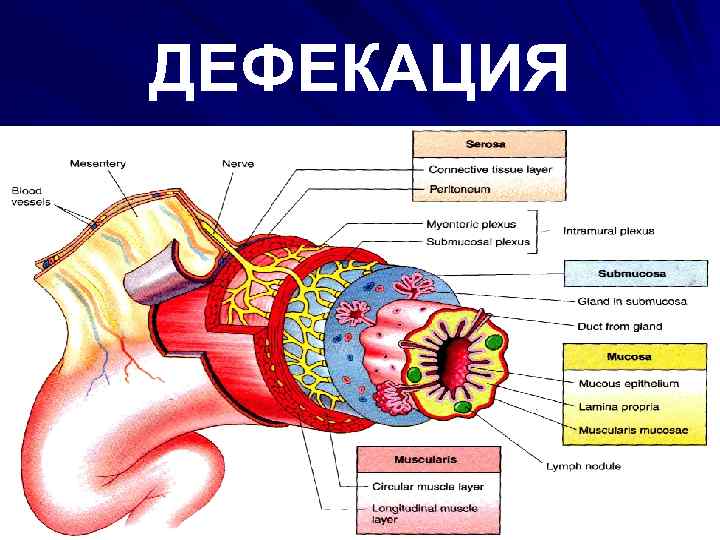

ДЕФЕКАЦИЯ

ДЕФЕКАЦИЯ